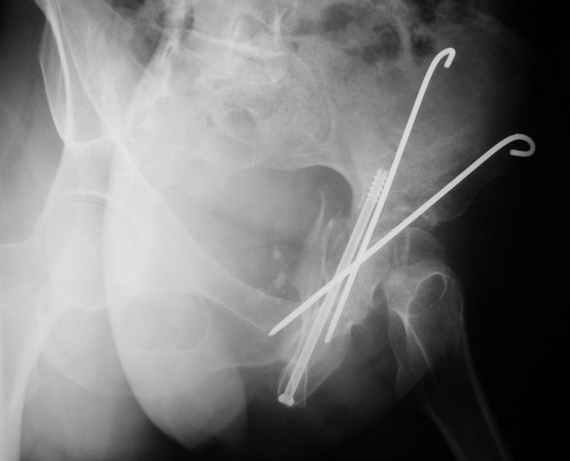

Anatoly F Lazarev 03 Сентябрь 2004, 22:18

Женя! Класный перелом. Отлично репонируется изнутри таза, но лучше фиксированть сзади. Классический перелом для двустороннего доступа.

Однако есть альтернатива. Репозиция из подвздошного доступа тазовыми щипцами с разнодлинными браншами или тазовым пистолетом, а фиксация задней колонны через седалищный бугор или тазрвыми винтами 4,5 или каннюлированными 6,5 или 7,3. По-моему я посылал на ортофорум такой снимок, когда жаловался на ишемический неврит седалищного нерва через сутки после операции. Не забудь про шейку бедра - мне кажется будет хорош длинный PFN любой фирмы, какую ты найдешь, а нет так UFN + miss a nail, как это здорово делают мои земляки - Ебурбуки. Пока.

Высылаю пример еще одного случая, остеосинтез пластиной из подвздошного доступа.